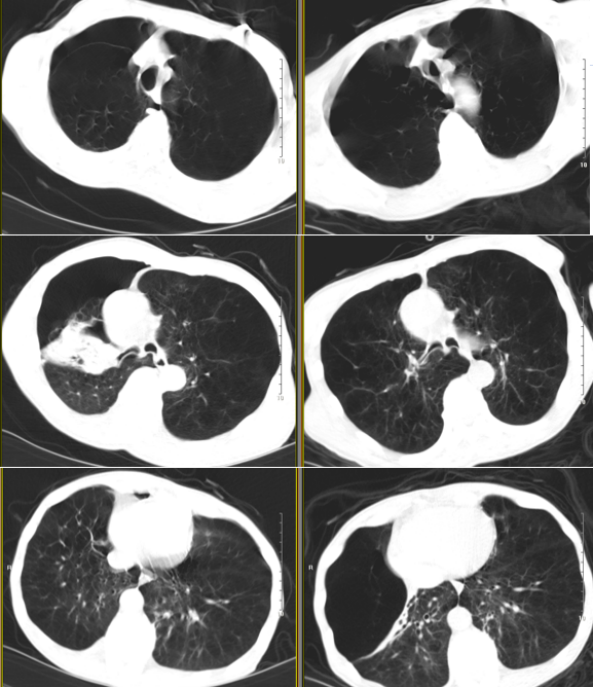

①呼吸困难:转运呼吸机辅助下呼吸频率26次/分,三凹征(脱机后加重);②Ⅱ型呼吸衰竭:血气分析提示pH 7.305,PaO2 96 mmHg,PaCO2 85.8 mmHg。③极重度阻塞性通气功能障碍:肺功能(外院1年前)提示FEV1/FVC 39.02%,FEV1/pre 14%,FVC/pre 28.3%。④全程管理:已戒烟10年,既往接受呼吸康复治疗。⑤极重度肺气肿:HRCT提示双肺不均质性肺气肿、右肺上叶巨大肺大疱(图1)

图片

图1  患者入我科后HRCT